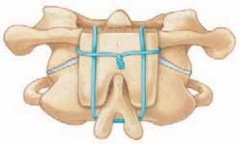

4. Each iliac crest graft is cut into a trapezoid-like shape (one end is narrower than the other) so that they can be wedged between the C1 and C2 posterior arches (

TECH FIG 5A

).

5. The grafts are snugly wedged into place. The wires are then tightened around the grafts, twisted, and cut (

TECH FIG 5B

TECH FIG 5•

Brooks arthrodesis.

A.

Lateral view demonstrating a wedge-shaped graft between the spinous processes to prevent hyperex-tension. The graft is shaped so that one end is narrower than the other to achieve a good fit.

B.

The grafts are snugly wedged between the C1 and C2 posterior arches, and the wires are tightened around the grafts.